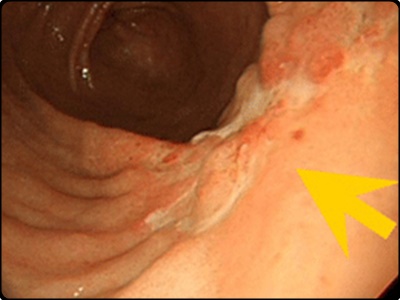

위암 초기증상: 소화기능 저하로 인한 위축성 위염

위산 분비가 감소하면서 동시에 소화기능이 저하되면 위 점막에 있는 세포가 변형을 일으키게 됩니다. 그리고 소화기능 저하라는 초기증상으로 나타나게 됩니다. 이는 위암 발생 위험도가 6배나 높습니다. 그리고 위축성 위염이 된 위는 정상인의 위로 회복이 불가능합니다.

하지만 위암으로 발전하지 않게 하도록 연속적인 관리가 필요합니다. 때문에 정기적으로 꾸준히 위내시경 검사를 하는 것이 중요합니다. 때문에 위암을 미리 예방하기 위해서는 나트륨 과다섭취를 피하는 것이 좋습니다. 가능하면 위벽을 자극하지 않도록 해야만 합니다. 위가 자극을 받게되면 위궤양을 일으키고 암세포를 생성하게 됩니다.